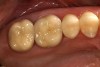

Figure 2  Preoperative occlusal view of teeth Nos. 2 and 3.

Figure 2

A patient presented with large amalgam restorations and recurrent caries on teeth Nos. 2 and 3 (Figure 2). After reviewing the treatment options, the patient chose all-ceramic crowns to restore the teeth. The specific all-ceramic crowns selected for the case were zirconia crowns. After completion of the crown preparations, soft-tissue retraction was achieved and the tooth surfaces were cleaned and dried (Figure 3). The teeth and soft tissues were isolated and lightly sprayed with a titanium-dioxide powder to create a reflective surface (Figure 4). The powder provides contrast points for scanning to enhance recording the 3-D models and to improve the speed of recording.